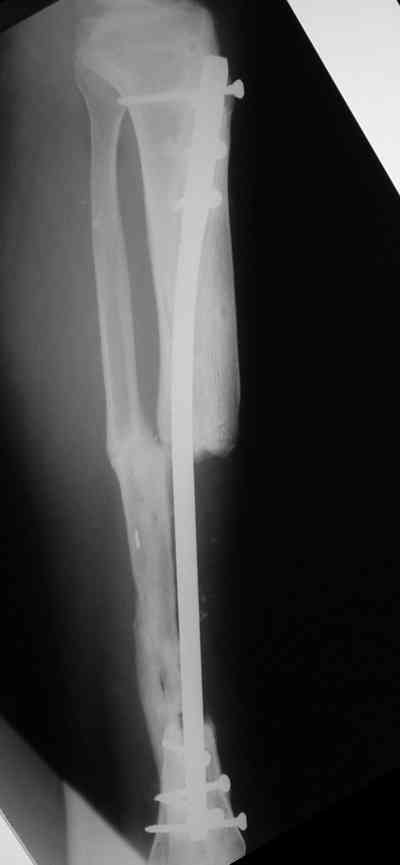

Владимир, свободная костная пластика на фоне свища вряд ли оправдана. Почему не рассматриваете вариант транспорта кости по Илизарову? Что собираетесь делать с латентной инфекцией? Одни антибиотики не помогут, необходима полноценная хирургическая обработка, Мы бы подумали о цементном спейсере с антибиотиками, бусах. После купирования инфекции переходить к замещению

дефекта: за счет удлинения концов б\б кости или тибиализации м\б. На начальном этапе фиксация только в аппарате, в последствие для удержания достигнутого можно перейти на фиксацию интрамедуллярным штифтом (см. вложенные файлы)

Как дополнение высылаю снимки и фото конечности, чтобы Вы могли оценить состояние м/т, и течение заболевания.